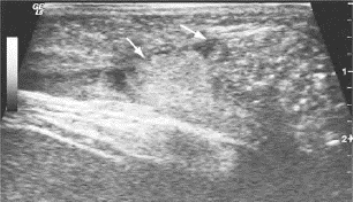

图32-2 腹壁疝声像图

箭头示肠管及网膜疝入腹壁